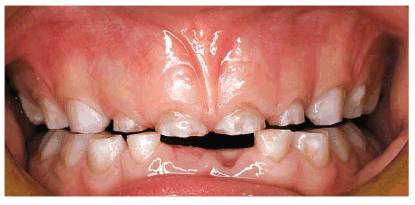

patient (Figures 17-1A to

C

Figure 17-1A to C: These photographs illustrate the complex dental condition of a 71-year-old male: (A) The palatal cervical regions of the maxillary anterior teeth exhibit sharp, wedge-like lesions that are characteristic of abfraction. These areas would be difficult, if not impossible, to have resulted from toothbrush abrasion. (B) The buccal aspects of the maxillary posterior teeth show smooth, concave configurations that are consistent with toothbrush abrasion and/or erosion. (C) The buccal surfaces of the mandibular teeth have lesions that possess components of both abfraction (sharp margins in the occlusal regions) and abrasion (concave geometry and gingival recession in the cervical regions).